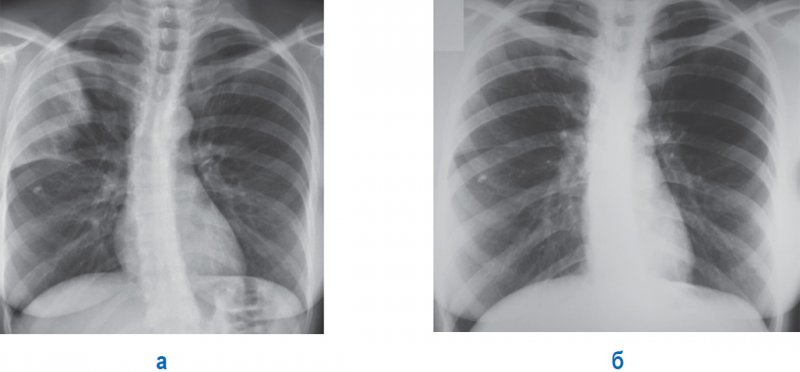

Рисунок 2. Плевропневмония. А – правосторонняя плевропневмония верхней доли (горизонтальная междолевая плевра справа утолщена и немного «вогнута» в сторону инфильтрации за счет незначительного уменьшения размера верхней доли). Б – рентгенограмма пациента через 10 дней антибактериальной терапии: отмечается выраженная положительная динамика, инфильтрация не обнаруживается, не определяется смещение междолевой плевры. В проекции средней доли справа определяется кальцинат